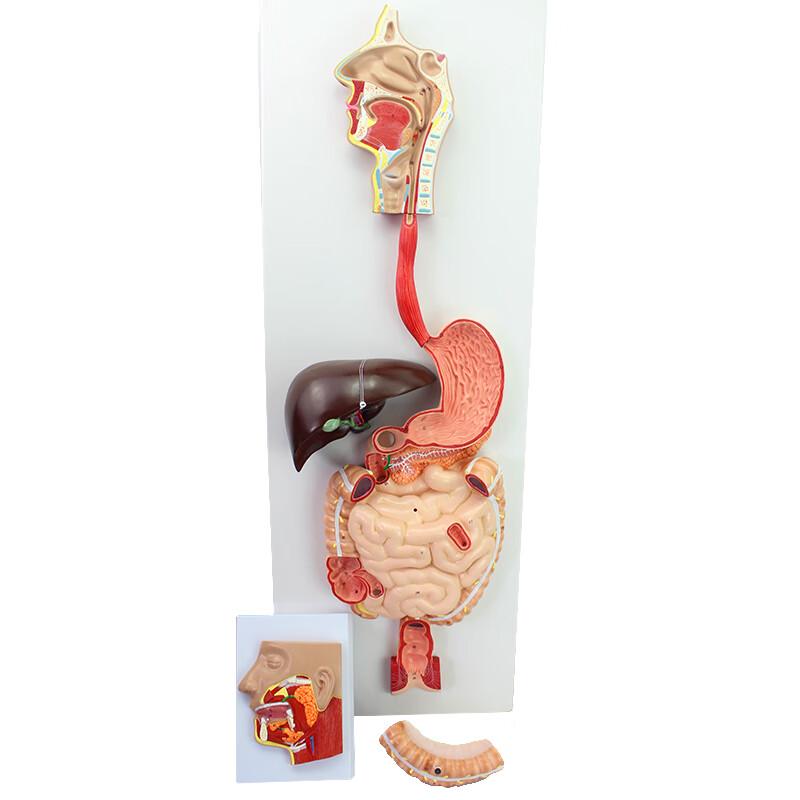

ENOVO Human Digestive System Anatomy Model

Купить за 69870 RUR

Следите за акциями и распродажами в июле 2026 от ООО ДЖУМ ИНН 7714448295 , www.joom.ru.

JDST online / / / подобные товары